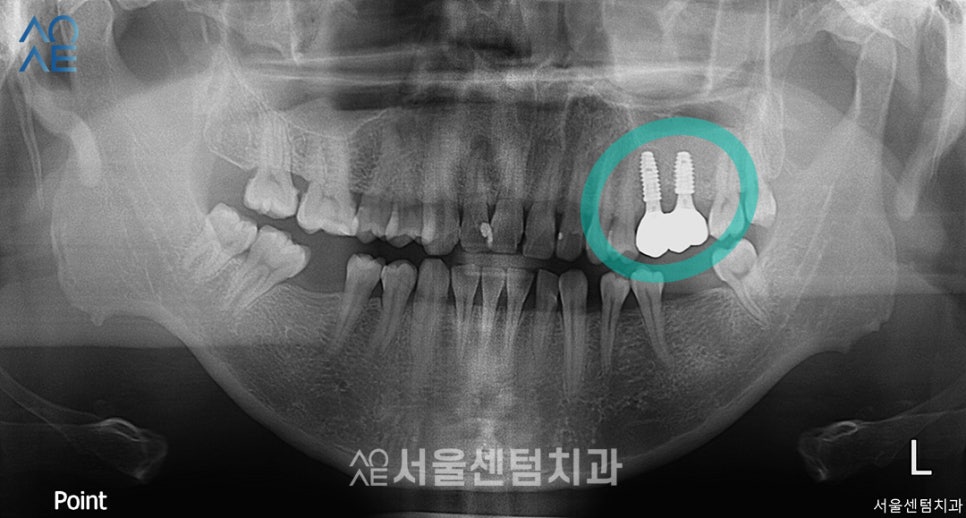

- 24

보철물 역시 안정적으로 잘 장착되었습니다.

물론 처음엔 임시로 부착하여

사용해보는 기간을 가졌습니다.

앞에서 말씀드린 헛구역질 증상이 심하신 것치고

상악동수술 임플란트식립

모두 잘 마무리 되었습니다.

이런 분들은 2차수술이 필요 없는

일체형 픽스처를 사용하여

진료 횟수를 줄여 드리는 것이 많은 도움이 됩니다.

보철물을 임시 접착제로 부착하여

약 10일정도 사용해보고

영구 부착을 하며 마무리해드렸습니다.